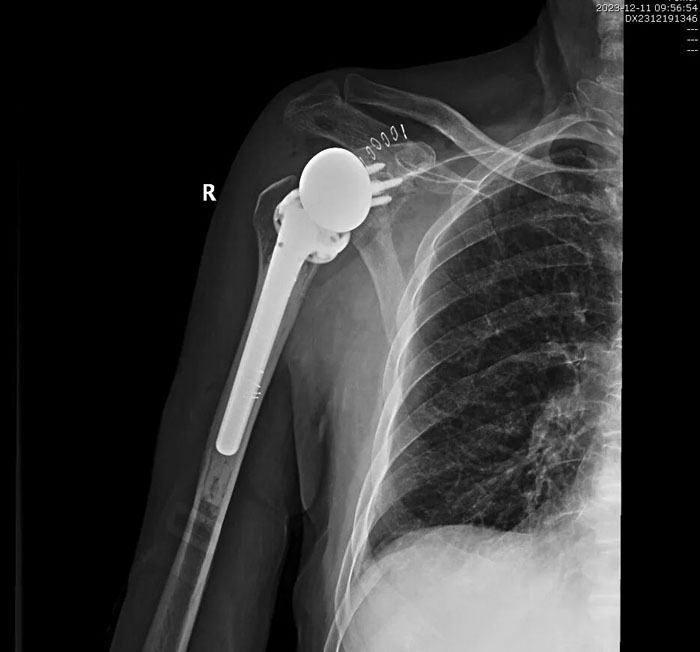

我院關節(jié)外科完成反式人工全肩關節(jié)置換術

近日,我院關節(jié)運動一病區(qū)成功完成反式人工全肩關節(jié)置換術(reverse total shoulder arthroplasty, RTSA),幫助肩痛患者重獲肩關節(jié)功能。

反式人工全肩關節(jié)置換術(reverse total shoulder arthroplasty, RTSA)是指肩關節(jié)假體的球形關節(jié)面放置于肩胛骨關節(jié)盂側(cè),而盂杯放置于肱骨近端的半限制性人工全肩關節(jié)。主要用于肩關節(jié)骨關節(jié)炎、類風濕性關節(jié)炎、肱骨頭缺血性壞死、肩袖關節(jié)病等,可明顯緩解患者肩部疼痛、改善上舉能力、恢復關節(jié)功能。

手術歷時2個小時順利完成,術后患者恢復良好,無并發(fā)癥發(fā)生,右肩關節(jié)功能明顯改善,患者對手術療效滿意。目前,患者已好轉(zhuǎn)出院,居家進行功能康復鍛煉中。

術后